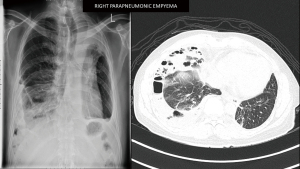

A 45-year-old male diagnosed to have stage 4 non-small cell lung cancer with brain metastases, left pleural effusion and complete obstruction of left main bronchus by tumour invasion. He underwent left main bronchial stenting with metallic stents followed by chemotherapy, immunotherapy and radiotherapy to his brain and left hilum. Six months later he developed chronic pseudomonas stage 3 empyema of the right chest due to chemotherapy induced neutropenia and colonisation of the metallic stent. He was septic and breathless due to his immunocompromised state and impaired lung capacity (Figure 2). As his general condition was poor, decision was made to perform decortication by VATS to decrease the morbidity (9,10). Lung isolation was obtained by selective bronchial blockage of the intermediate bronchus to allow ventilation of the right upper lobe bronchus while surgery was conducted by VATS. The selective lobar isolation was obtained by using Arndt blocker endotracheal tube with the blocker introduced into the intermediate bronchus to isolate the lower and middle lobes to be collapsed whilst the upper lobe continues to be ventilated for adequate oxygenation (Figure 3 & Video 1). This allowed adequate safe oxygenation and exposure for decortication to be performed by VATS (Video 2). The surgical visceral pleural plane in the entrapped lung was better delineated by intermittent inflation of the lung by insufflating oxygen through the blocker channel without deflating the blocker balloon. Post-operative recovery was uneventful and was discharged well with resolution of infection (Figure 4). He was started on immunotherapy with good tumour response. He has remained cancer and infection free 4 years post-surgery.